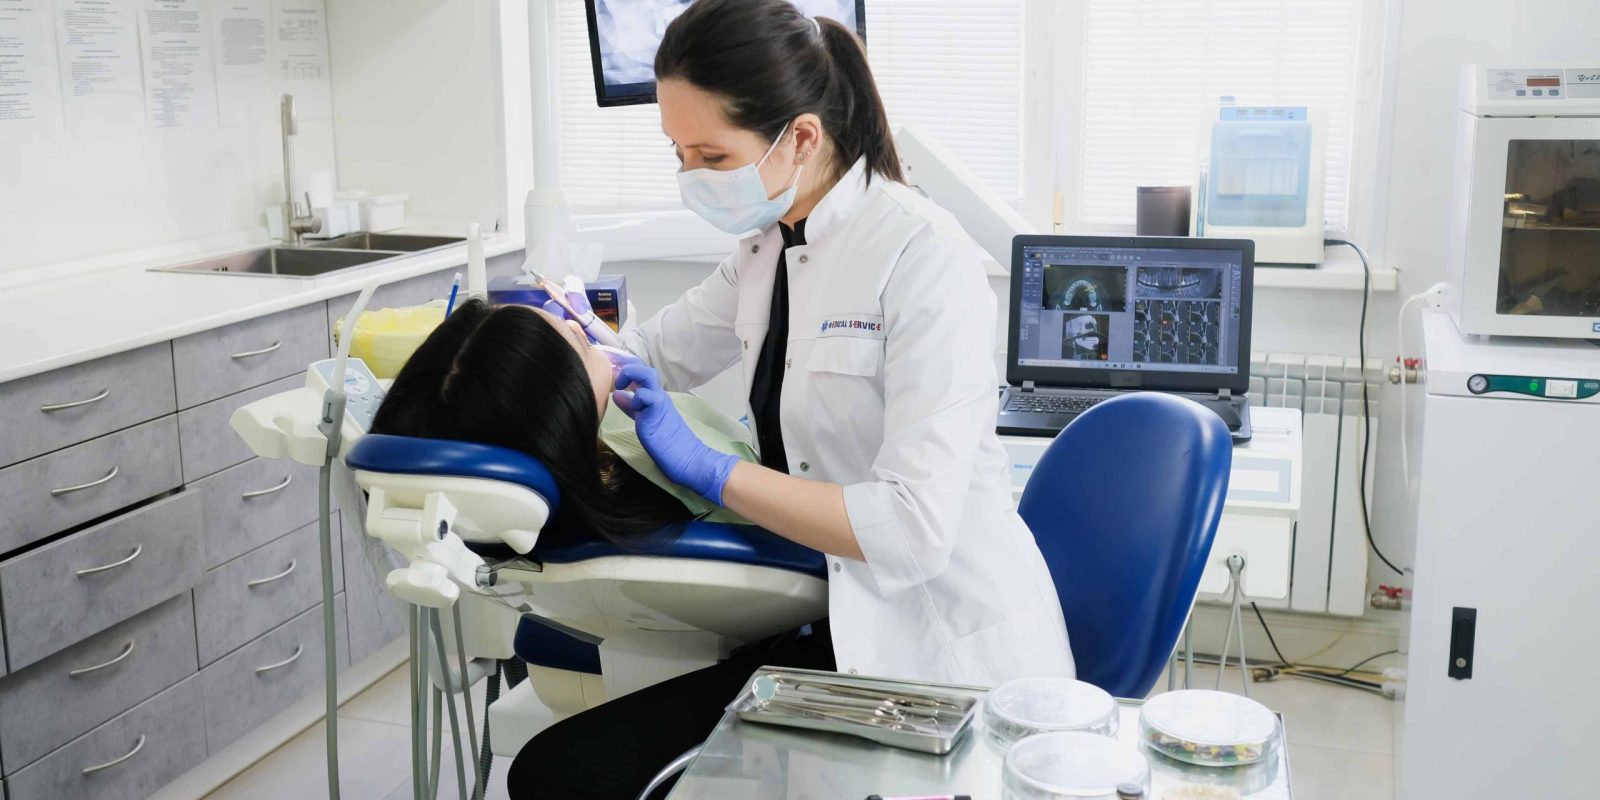

Endodoncia

Es la práctica odontológica que consiste en la extirpación de la pulpa dental y el posterior relleno y sellado de la cavidad pulpar con un material inerte.